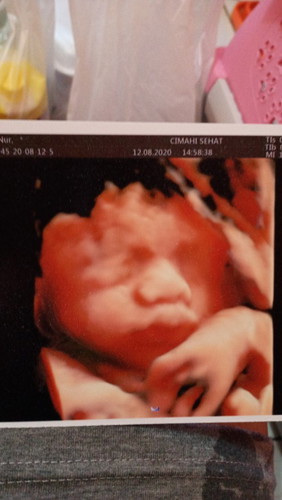

Assalamu'alaikum bunda2..sp yg hpl besok tp blm jg mules2 🥺 Gimana ya bun..udh pgn bgt buat ketemu baby tp kok blm ada tanda2 mau lahiran..sp yg sama kaya aku 😢 jujur anak pertama jd suka worry dan neghtink trs..apalagi org2 bilng "kenapa dia udah kamu belum pdhl hamil bareng 😓"#bantusharing